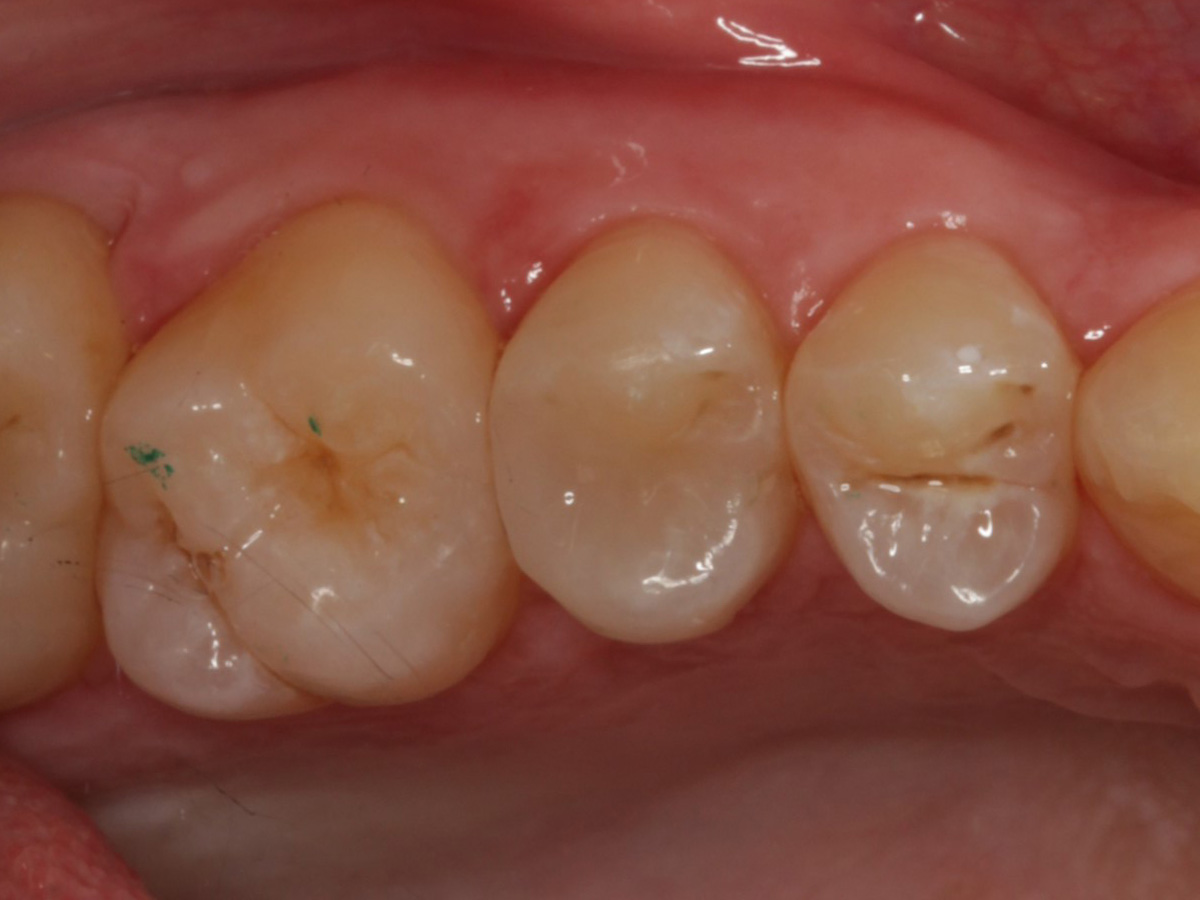

Abbildung 1

Approximalraumkaries an Zahn 25 distal